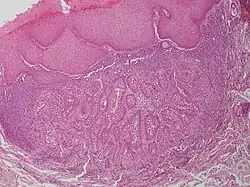

Warty dyskeratoma, also known as an Isolated dyskeratosis follicularis,[1]: 777  is a benign[2] epidermal proliferation with distinctive histologic findings that may mimic invasive squamous cell carcinoma[3] and commonly manifests as an umbilicated (Having a central mark or depression resembling a navel) lesion with a keratotic plug,[4] WD have some histopathologic similarities to viral warts but it's not caused by HPV and the majority of these lesions display overall histopathologic features consistent with a follicular adnexal neoplasm.[5] Usually limited to the head, neck,[6] scalp[7] or face and vulva.[6] Lesions are generally solitary and sporadic and may be associated with a follicular unit. Oral involvement,[4] particularly the hard palate, and genital involvement have been reported. it can also be thought of as one of the manifestations of focal acantholytic dyskeratosis, an epidermal reaction pattern that can be seen in several disorders, including Darier's disease and Grover's disease.[8]: 639  But the main Difference between Darier disease and Warty dyskeratoma, is that Darier disease inherited dermatosis (autosomal dominant) consisting of multiple keratotic papules on the face, trunk, and extremities, while WD occurs as an isolated, noninherited, single keratotic nodule mainly confined to the head and neck as mentioned earlier.[6]